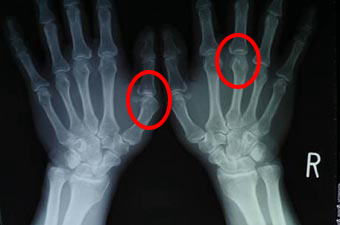

ヘバーデン結節に似た病気 乾癬による手指の関節炎倉石整形外科クリニック 長野市若穂 リハビリテーション科。

20代で指の骨が破壊される「乾癬性関節炎」、新薬アプレミラストの効果は?MEDLEYニュース。

肌がガサガサ、指も曲がる乾癬性関節炎に「幻の薬」トルツの効果は?MEDLEYニュース。